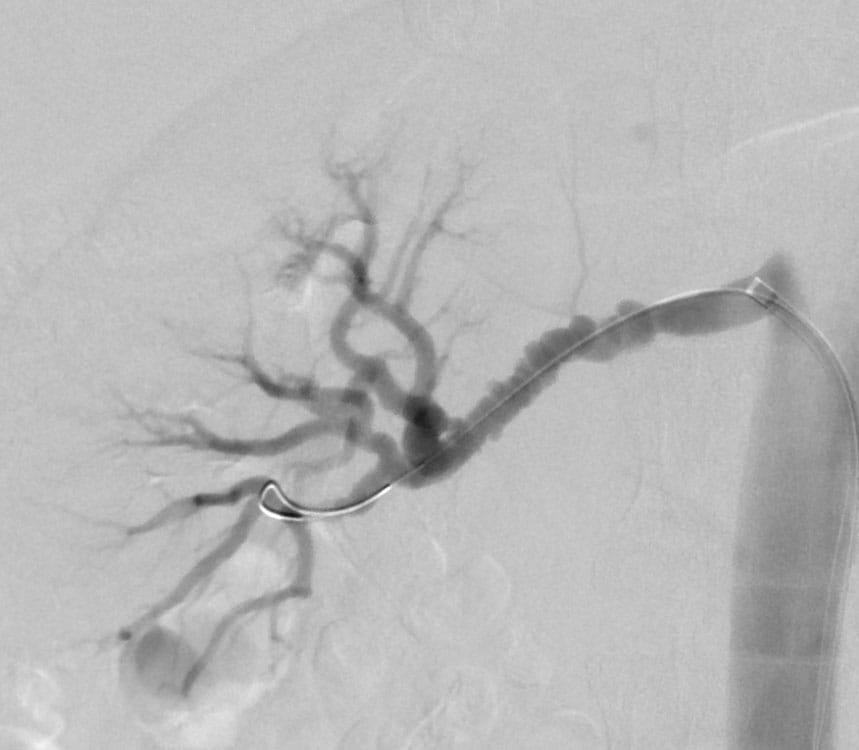

Image of classical "string of beads" of multifocal type FMD in the right renal artery in a patient undergoing an angioplasty procedure for hypertension. Caption: Shown is the classical "string of beads" of multifocal type FMD in the right renal artery in a patient undergoing an angioplasty procedure for hypertension.